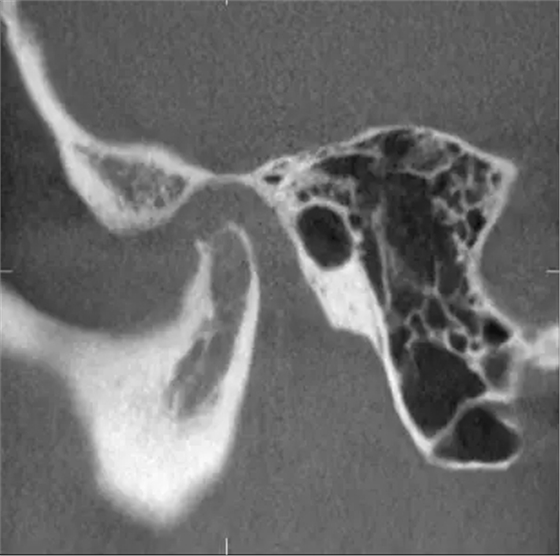

完全埋在牙槽骨里的下頜智齒,它本身倒是不出問題。但是這些近中或水平阻生的智齒,會推擠下頜第二磨牙,導致第二磨牙伸長:

然后,第二磨牙造成咬合干擾、早接觸,前牙開 牙合…………

甚至髁突吸收: